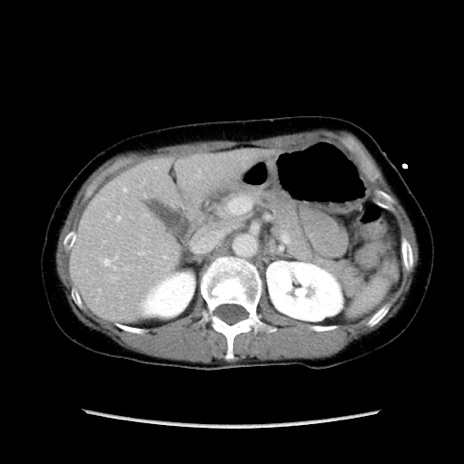

症例32(横断像)

【症例】40歳代 女性

【主訴】上腹部痛、嘔気・嘔吐

【現病歴】約9時間前頃から急に上腹部痛、嘔気、嘔吐が出現。改善しないため救急要請。

【既往歴】子宮頚癌(広汎子宮全摘術、放射線療法)、腸閉塞

【身体所見】腹部:平坦、軟、腸雑音亢進、上腹部を中心に腹部全体に圧痛あり。

【データ】WBC 8400、CRP 0.03